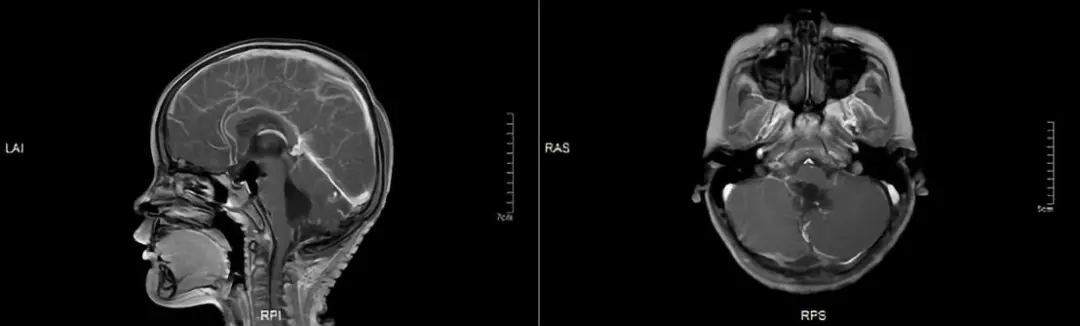

术后第一天MRI图示(图2):

幕上脑室丰满;第四脑室扩大,形态不规则,边缘毛糙,内见斑片短T1短T2信号,四脑室周围脑实质呈长T2信号影改变,延髓后缘信号稍欠均匀;大脑半球、丘脑、小脑内均未见异常MR信号影,双侧基底节区结构对称、清晰;中线结构居中。后枕部信号欠均匀。

图2 术后第一天磁共振(MRI)图